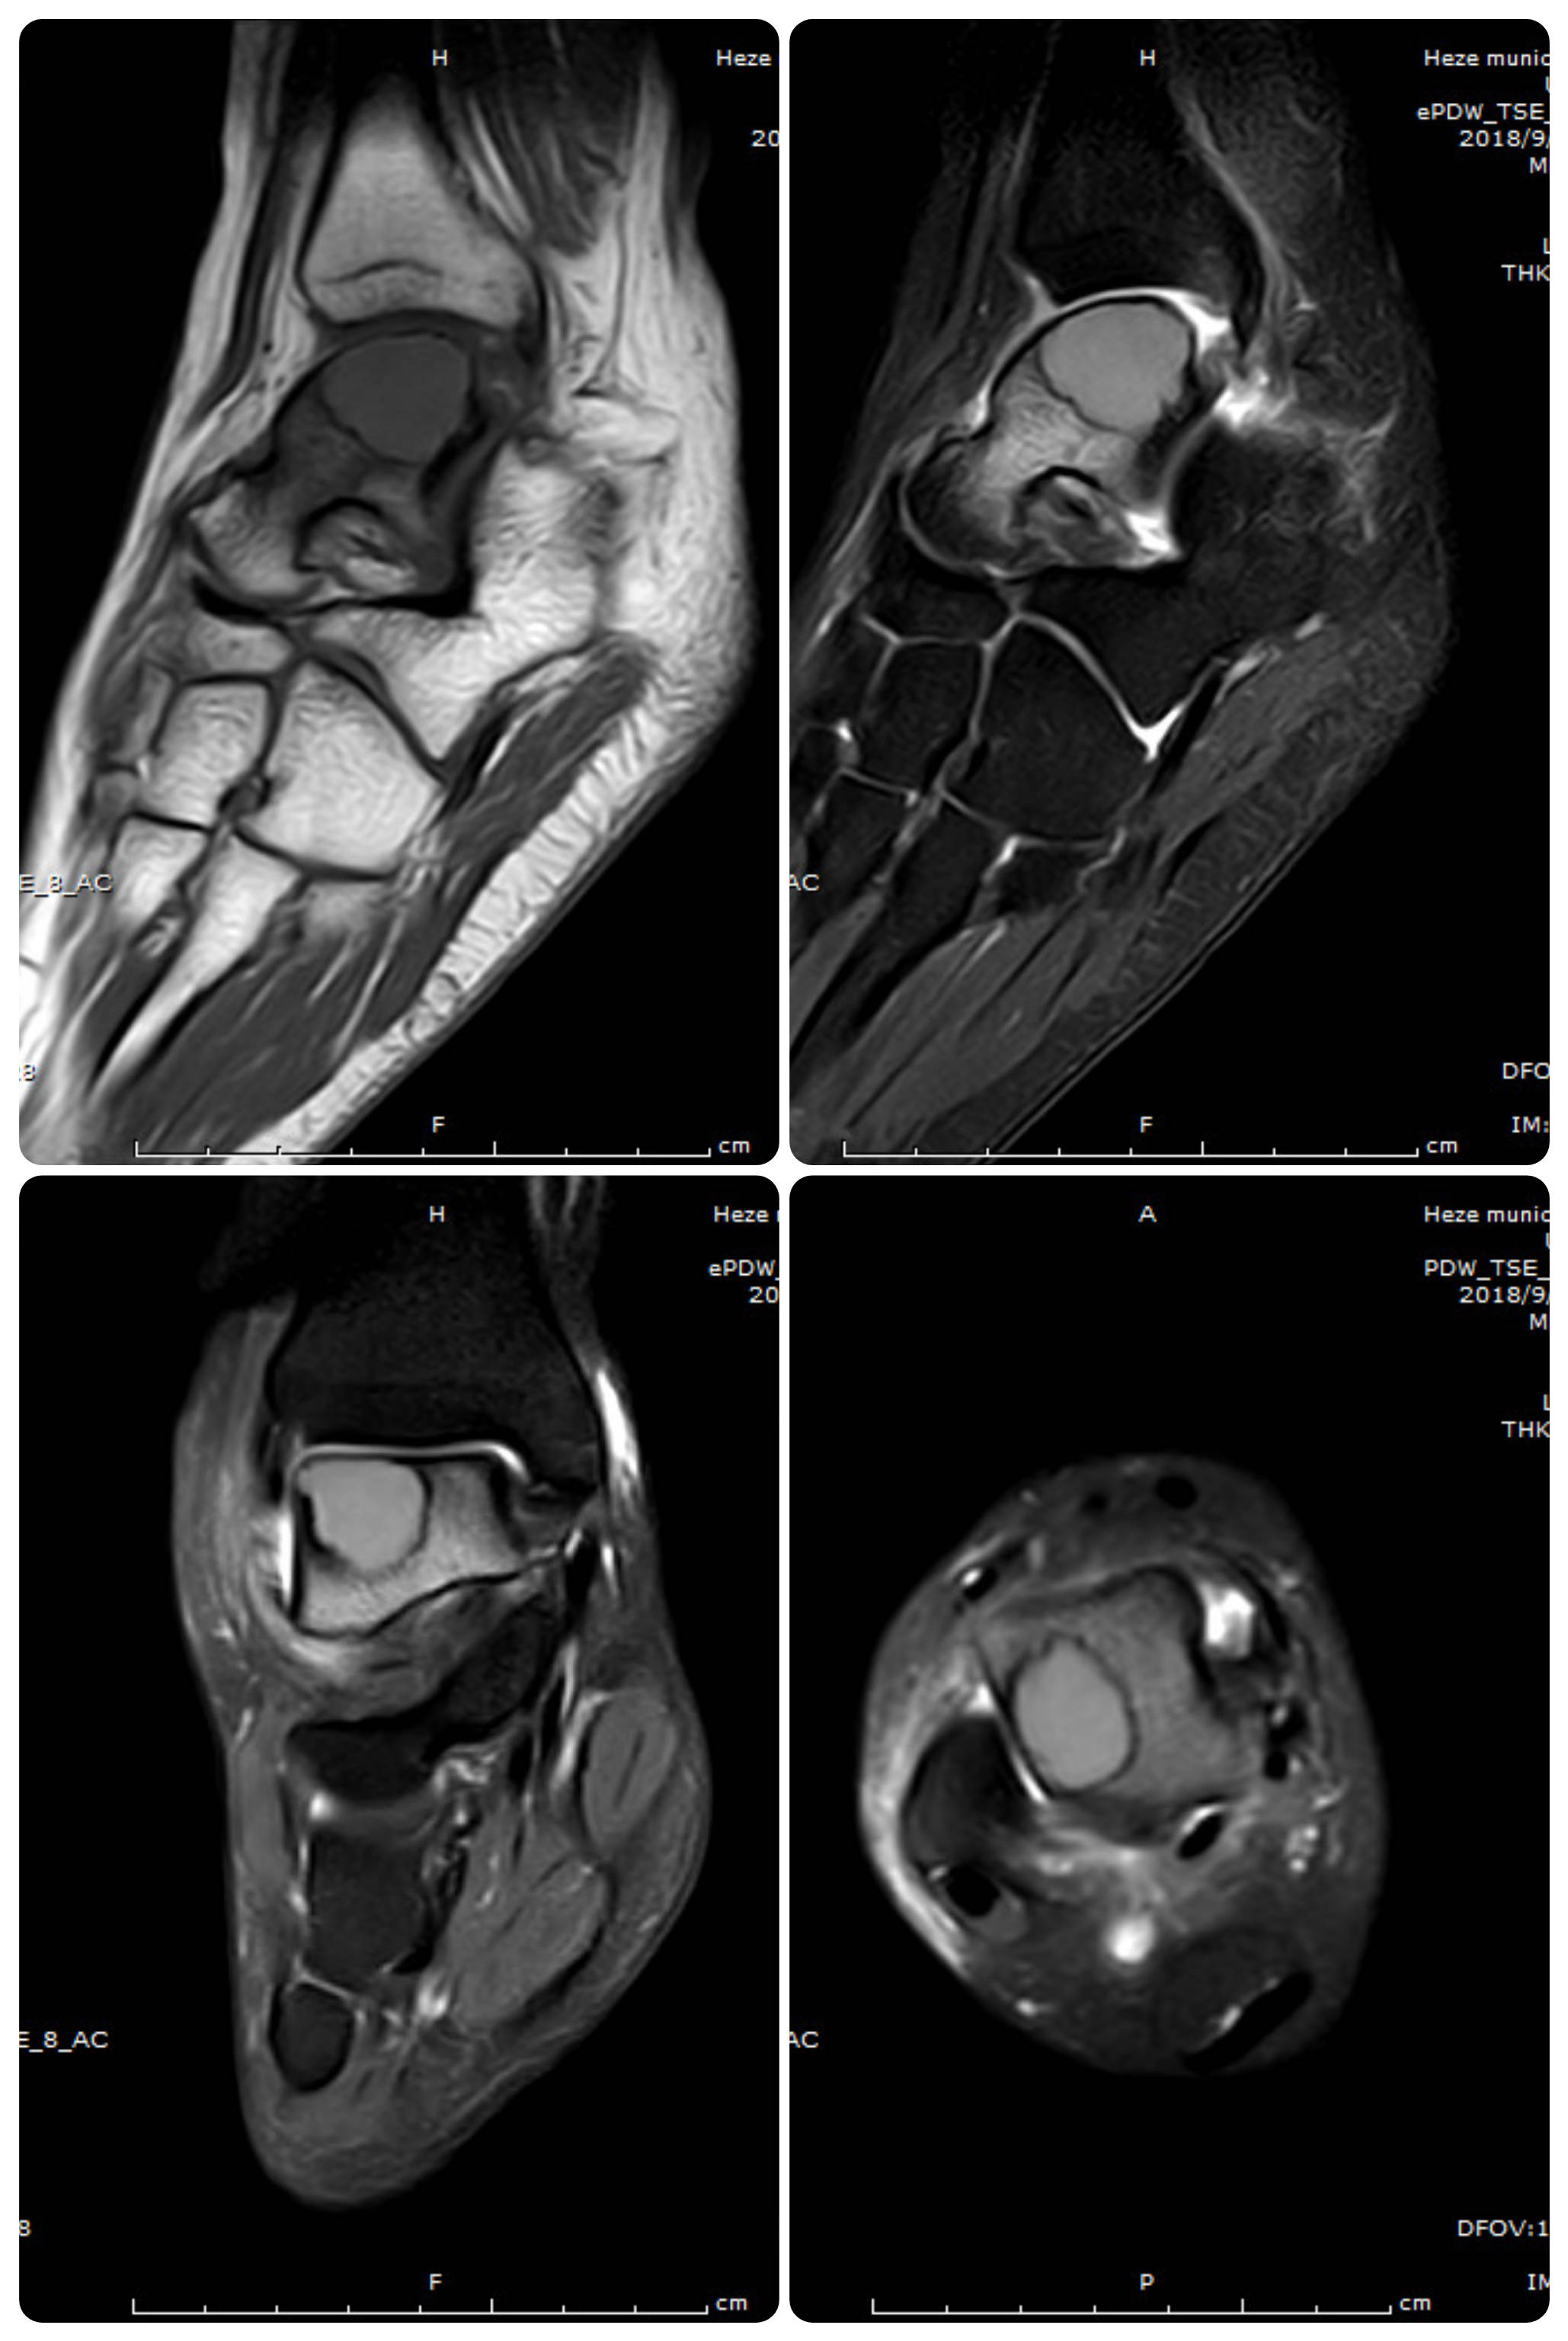

【病例】骨巨细胞瘤1例ct及mr影像表现

图片尺寸960x720